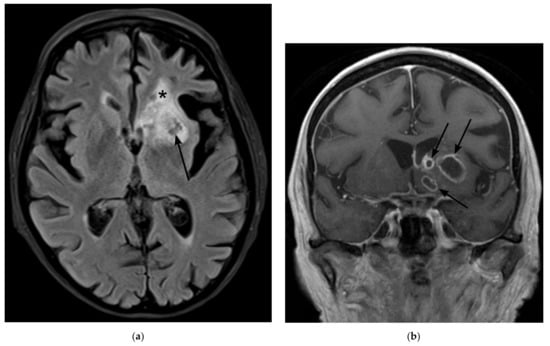

Figure 4.

Magnetic Resonance Imaging (MRI) on day 251 after initial admission to the hospital (a) Fluid attenuated inversion recovery (FLAIR) shows regressing lesions with mixed T2 signal (arrow) and a hypointense tissue defect at the former site of the abscesses (star). (b) Contrast-enhanced T1-weighted image in corona shows regressive enhancement of the lesions.